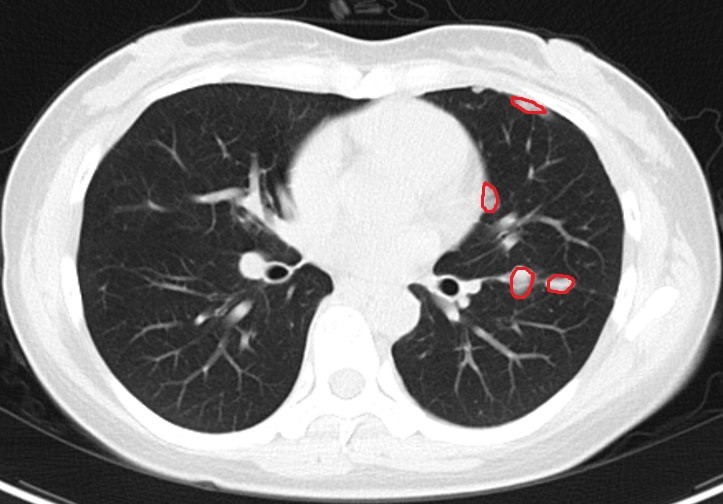

入院后ct

化疗 免疫治疗晚期肺癌有效病例报告 - 好大夫在线